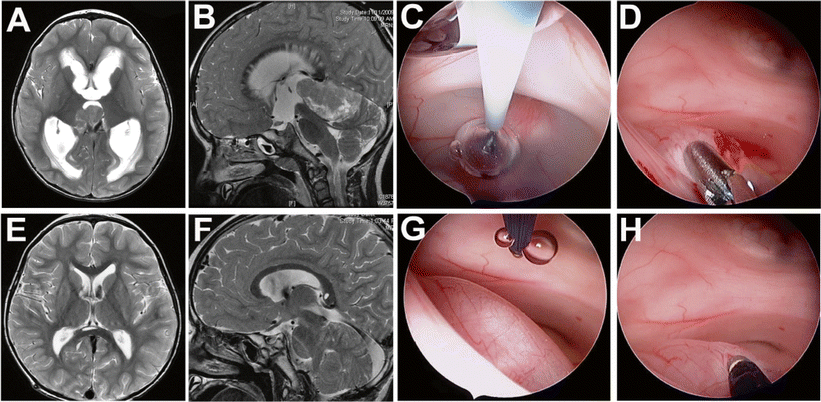

Seven-year-old with tuberous sclerosis and intraventricular tubers and a radiologically growing subependymal giant cell astrocytoma. The coronal (a) and axial post contrast MRI (b) demonstrates the intraventricular lesions. Endoscopic view of the lesions (c) and endoscopic-assisted microsurgical resection of the tumor (d)

Three-year-old presenting with progressive imbalance, nausea, and vomiting. Initial MRI demonstrated a large pineal region tumor extending into the third ventricle and significant obstructive hydrocephalus with periventricular edema (a, b). An endoscopic third ventriculostomy (c) followed by a tumor biopsy (d) was performed. The pathological diagnosis was pinealoblastoma, and a supracerebellar infratentorial approach was chosen for tumor resection. Follow-up MRI demonstrated resolution of the hydrocephalus (e) and a gross total tumor resection was achieved (f). To reach the tumor, a burr hole was placed slightly more frontal than the classic Kocher’s point. This, together with an enlarged foramen of Monro, allowed access to the posterior part of the third ventricle. To improve visualization and control of endoscopic instruments in the tumor, the endoscope was rotated 180°, placing the working channel close the lesion. g Prior to rotation, note instrument at 12 o’clock away from lesion. h Instrument at 6 o’clock with good access to the tumor